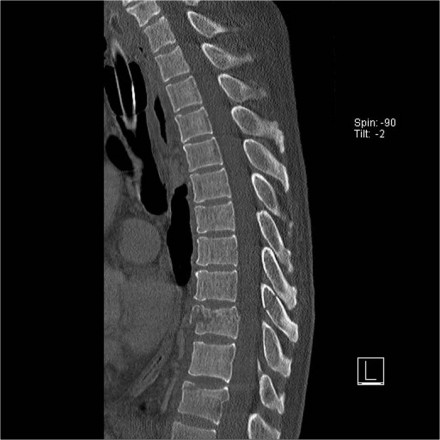

The images show two cases of osteochondrosis.

On the right with kyphosis.